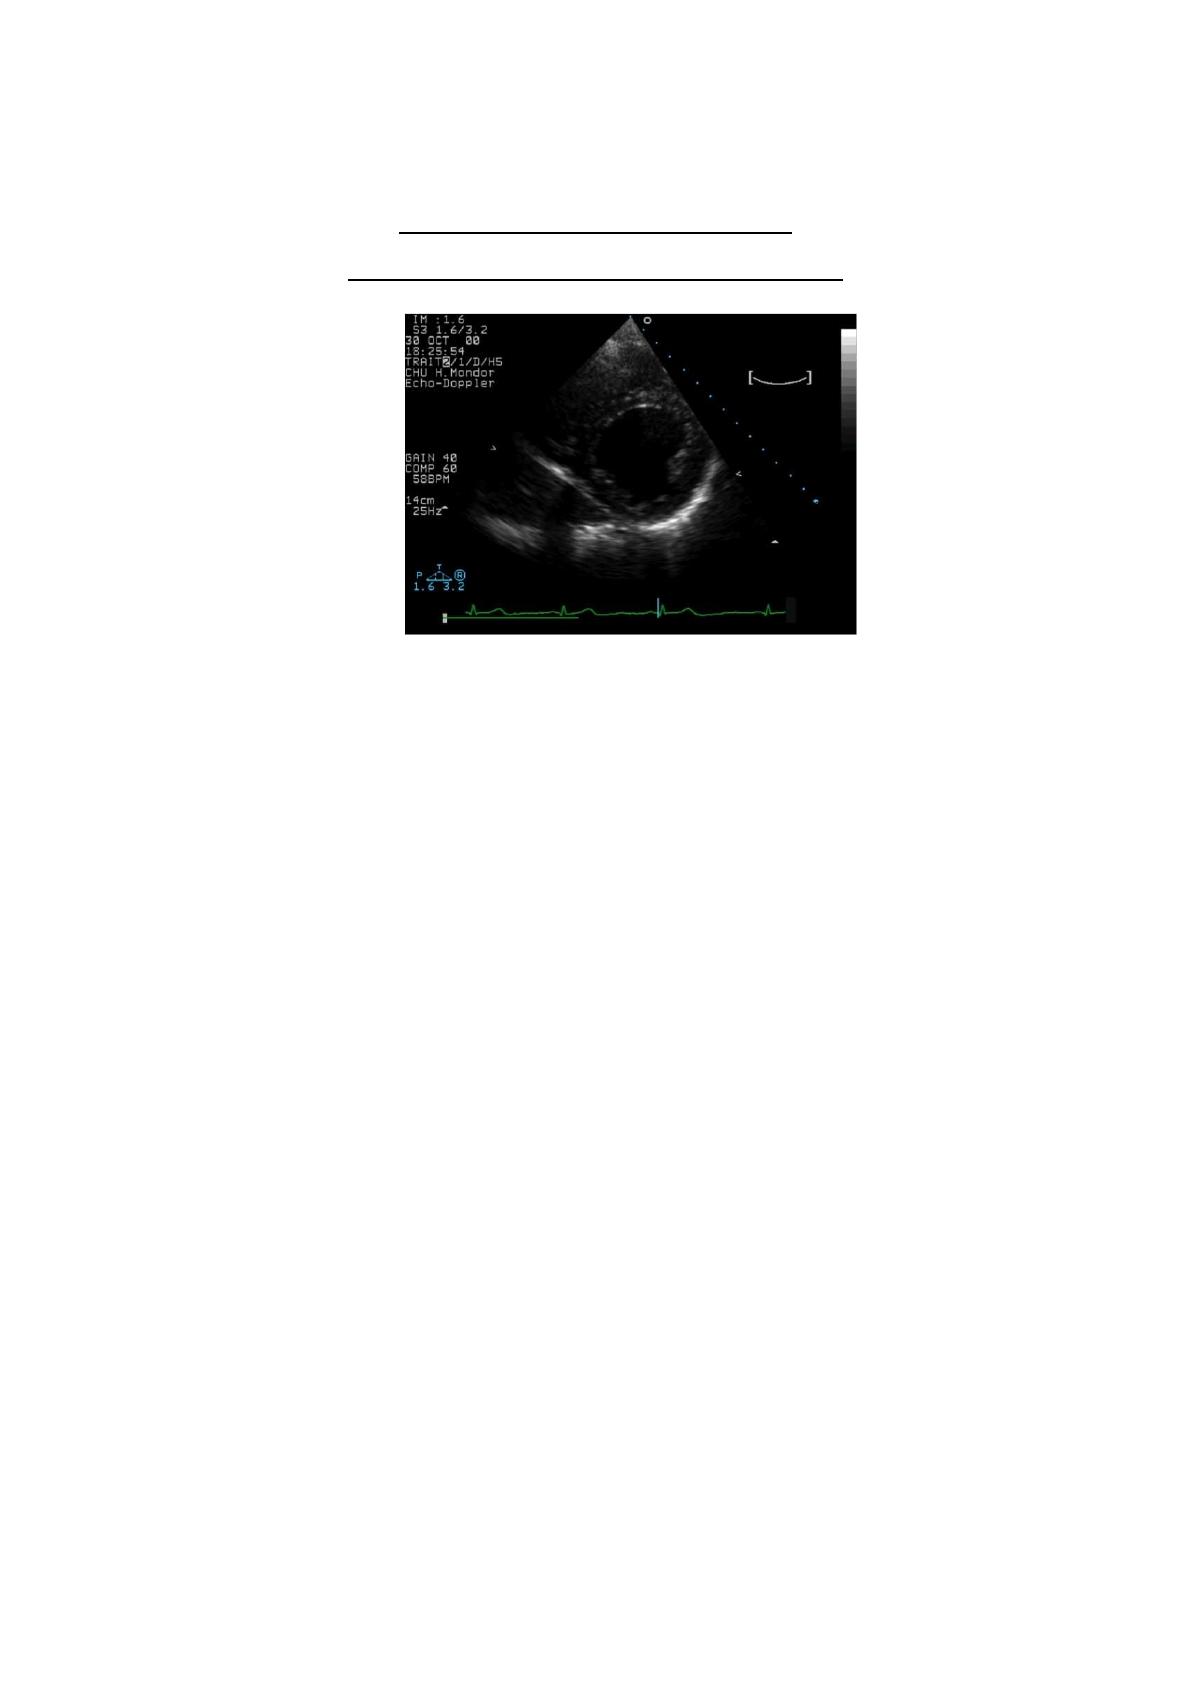

- Cas clinique n°2 :

Vous recevez une patiente de 76 ans, adressée par son médecin traitant pour une suspicion

de phlébite.

Dans ses ATCD, on note : une phlébite il y a 15 ans, une hypertension artérielle et une

hypercholestérolémie. Son traitement de fond comprend Loxen 50 et Crestor.

Elle vous explique que depuis 8 jours, sa jambe gauche lui fait mal et qu’elle « gonfle » le

soir. Le médecin traitant consulté hier, lui a fait une piqure et lui a demandé de faire un

examen en urgence.

A l’examen, la patiente est apyrétique, les constantes prises à l’IOA sont normales. Le mollet

et la cheville gauche sont discrètement augmentés de volume, le ballotement du mollet est

diminué et le Homans est négatif.

- A/ Comment complétez-vous votre examen clinique avec l’échographie ?